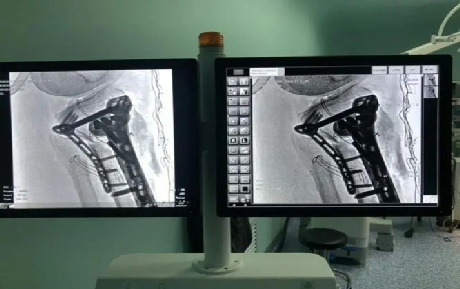

c型臂x光机,顾名思义该设备有C型的机架,产生x射线的球管,采集图像的影像增强器和CCD摄像机,以及图像处理的工作站组成。主要用于各种手术中的造影,摄影等工作在手术室中使用越来越广泛,可以直接应用于骨科手术中的术中定位,诊断检查整骨、复位、打钉等的效果,以及配合各种微创手术的开展、取出体内金属异物等治疗中发挥了独特的作用。能显著提高手术成功率,缩短手术时间,减少手术创伤及出血,亦减轻患者痛苦,有利于骨折愈合,更是避免了医院的医疗纠纷。

C 形臂发出的射线进入病人身体后,只有 1%左右的射线穿过病人到达增强器表面,如下图

当射线进入人体后,1%穿过人体进入增强器,其余 80%-90%的射线被病人吸收,10%-20%的射线被人体散射。如下图